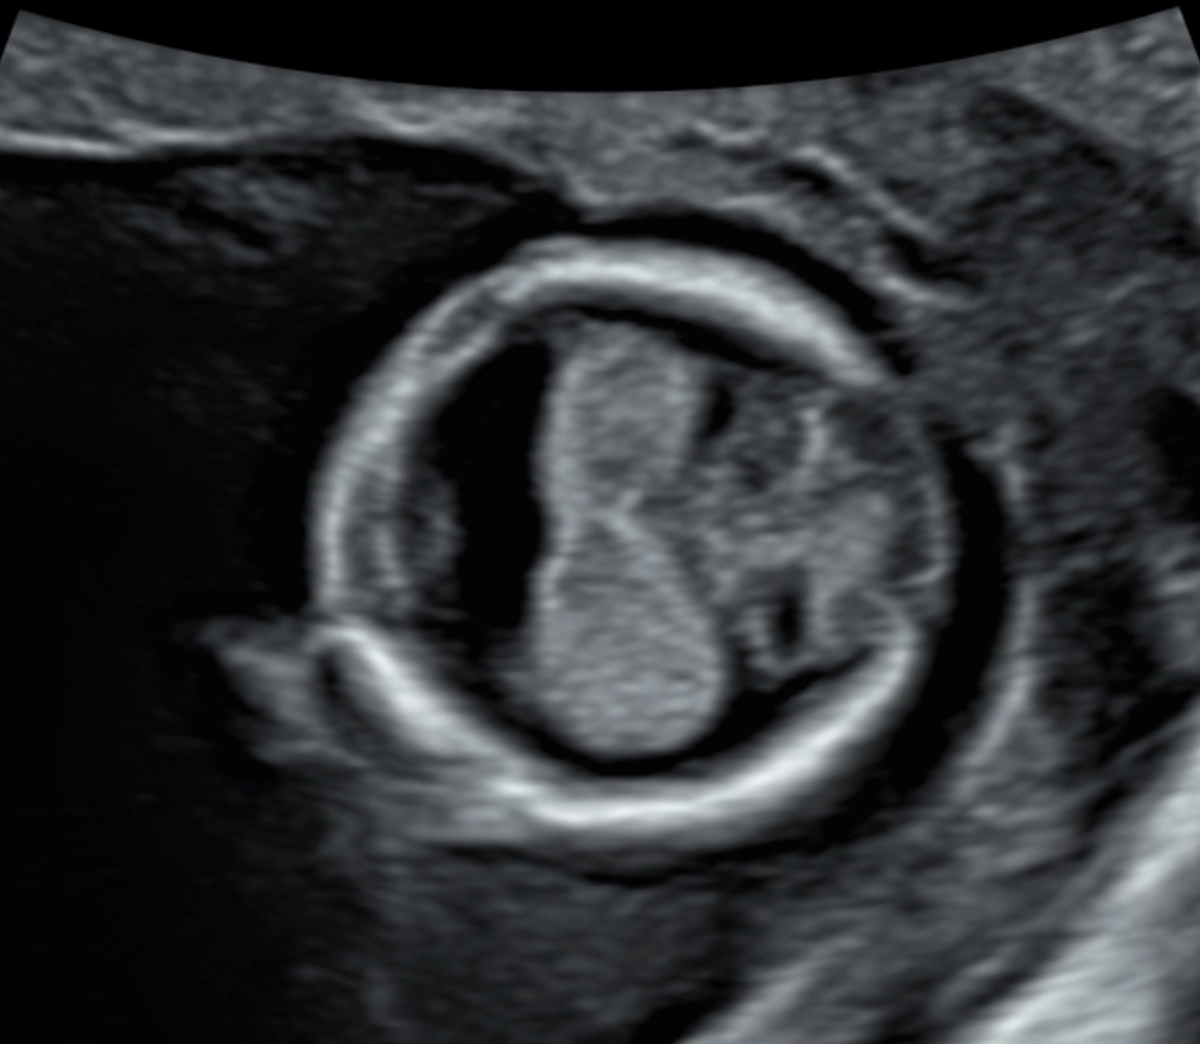

First trimester screening is not limited to detecting trisomies 13/18/21; it is essential for early identification or exclusion of many major structural anomalies (see figures 3–5). According to the current Swiss guidelines [3], combined testing for trisomies should be offered only when no significant malformations have been found and when nuchal translucency is below the 95th centile. Otherwise, diagnostic procedures should be offered.

Figure 4Holoprosencephaly in a 13-week foetus: abnormal circular head shape, no midline, fused choroid plexus.